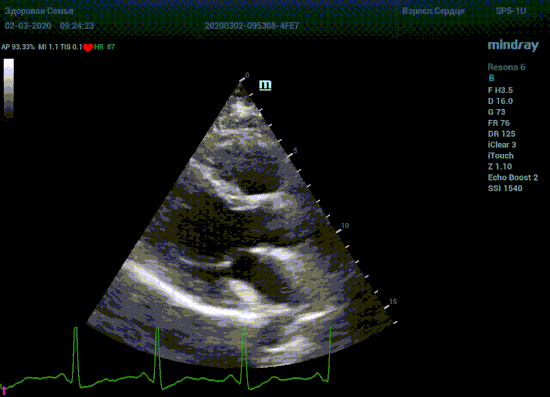

Подбор подобающей терапии и оценка её динамики на базе расчета массы миокарды рутинная задача эхокардиографии. Для измерения массы нужен кадр конца диастолы. На глазок или точно, по ЭКГ каналу, выбрать диастолу? Гипертрофия миокарда или его ремоделирование? Ремоделирование или норма? Решает каждый измеренный миллиметр, даже каждая его десятая. Лишние доли секунды приведут к началу сокращения миокарда и его утолщению, в результате -гипердиагностика.

Терапия наиболее широкая область применения, однако взрослая кардиохирургия так же важное направление современной медицины. Оперировать аортальный стеноз, или же площадь клапана достаточная? Необходимо рассчитать площадь аортального клапана по уравнению непрерывности потока. Для этого нужно измерить на зуме выносящий тракт левого желудочка (LVOT) в середине систолы. Будем угадывать момент или возьмем середину Т зубца по ЭКГ? Доверимся интуиции при определении показаний к оперативному лечению или науке?

Детская кардиохирургия не исключение. Наиболее актуальная проблема — это дефекты межпредсердной и межжелудочковой перегородок, а также открытый артериальный проток. Не верная оценка гемодинамической значимости приведет к перегрузке правых отделов сердца и ряду осложнений, в случае если не прооперировать вовремя. Отправлять маленького ребенка под нож или подождать пока дефект перегородки зарастет сам? Ждем осложнений или ждать безопасно? На эти вопросы ответит Qp/Qs соотношение, рассчитанное методом эхокардиографии. Для этого необходимо рассчитать ударные объемы выносящих трактов желудочков, опять же на середине систолы – середине Т–зубца ЭКГ.